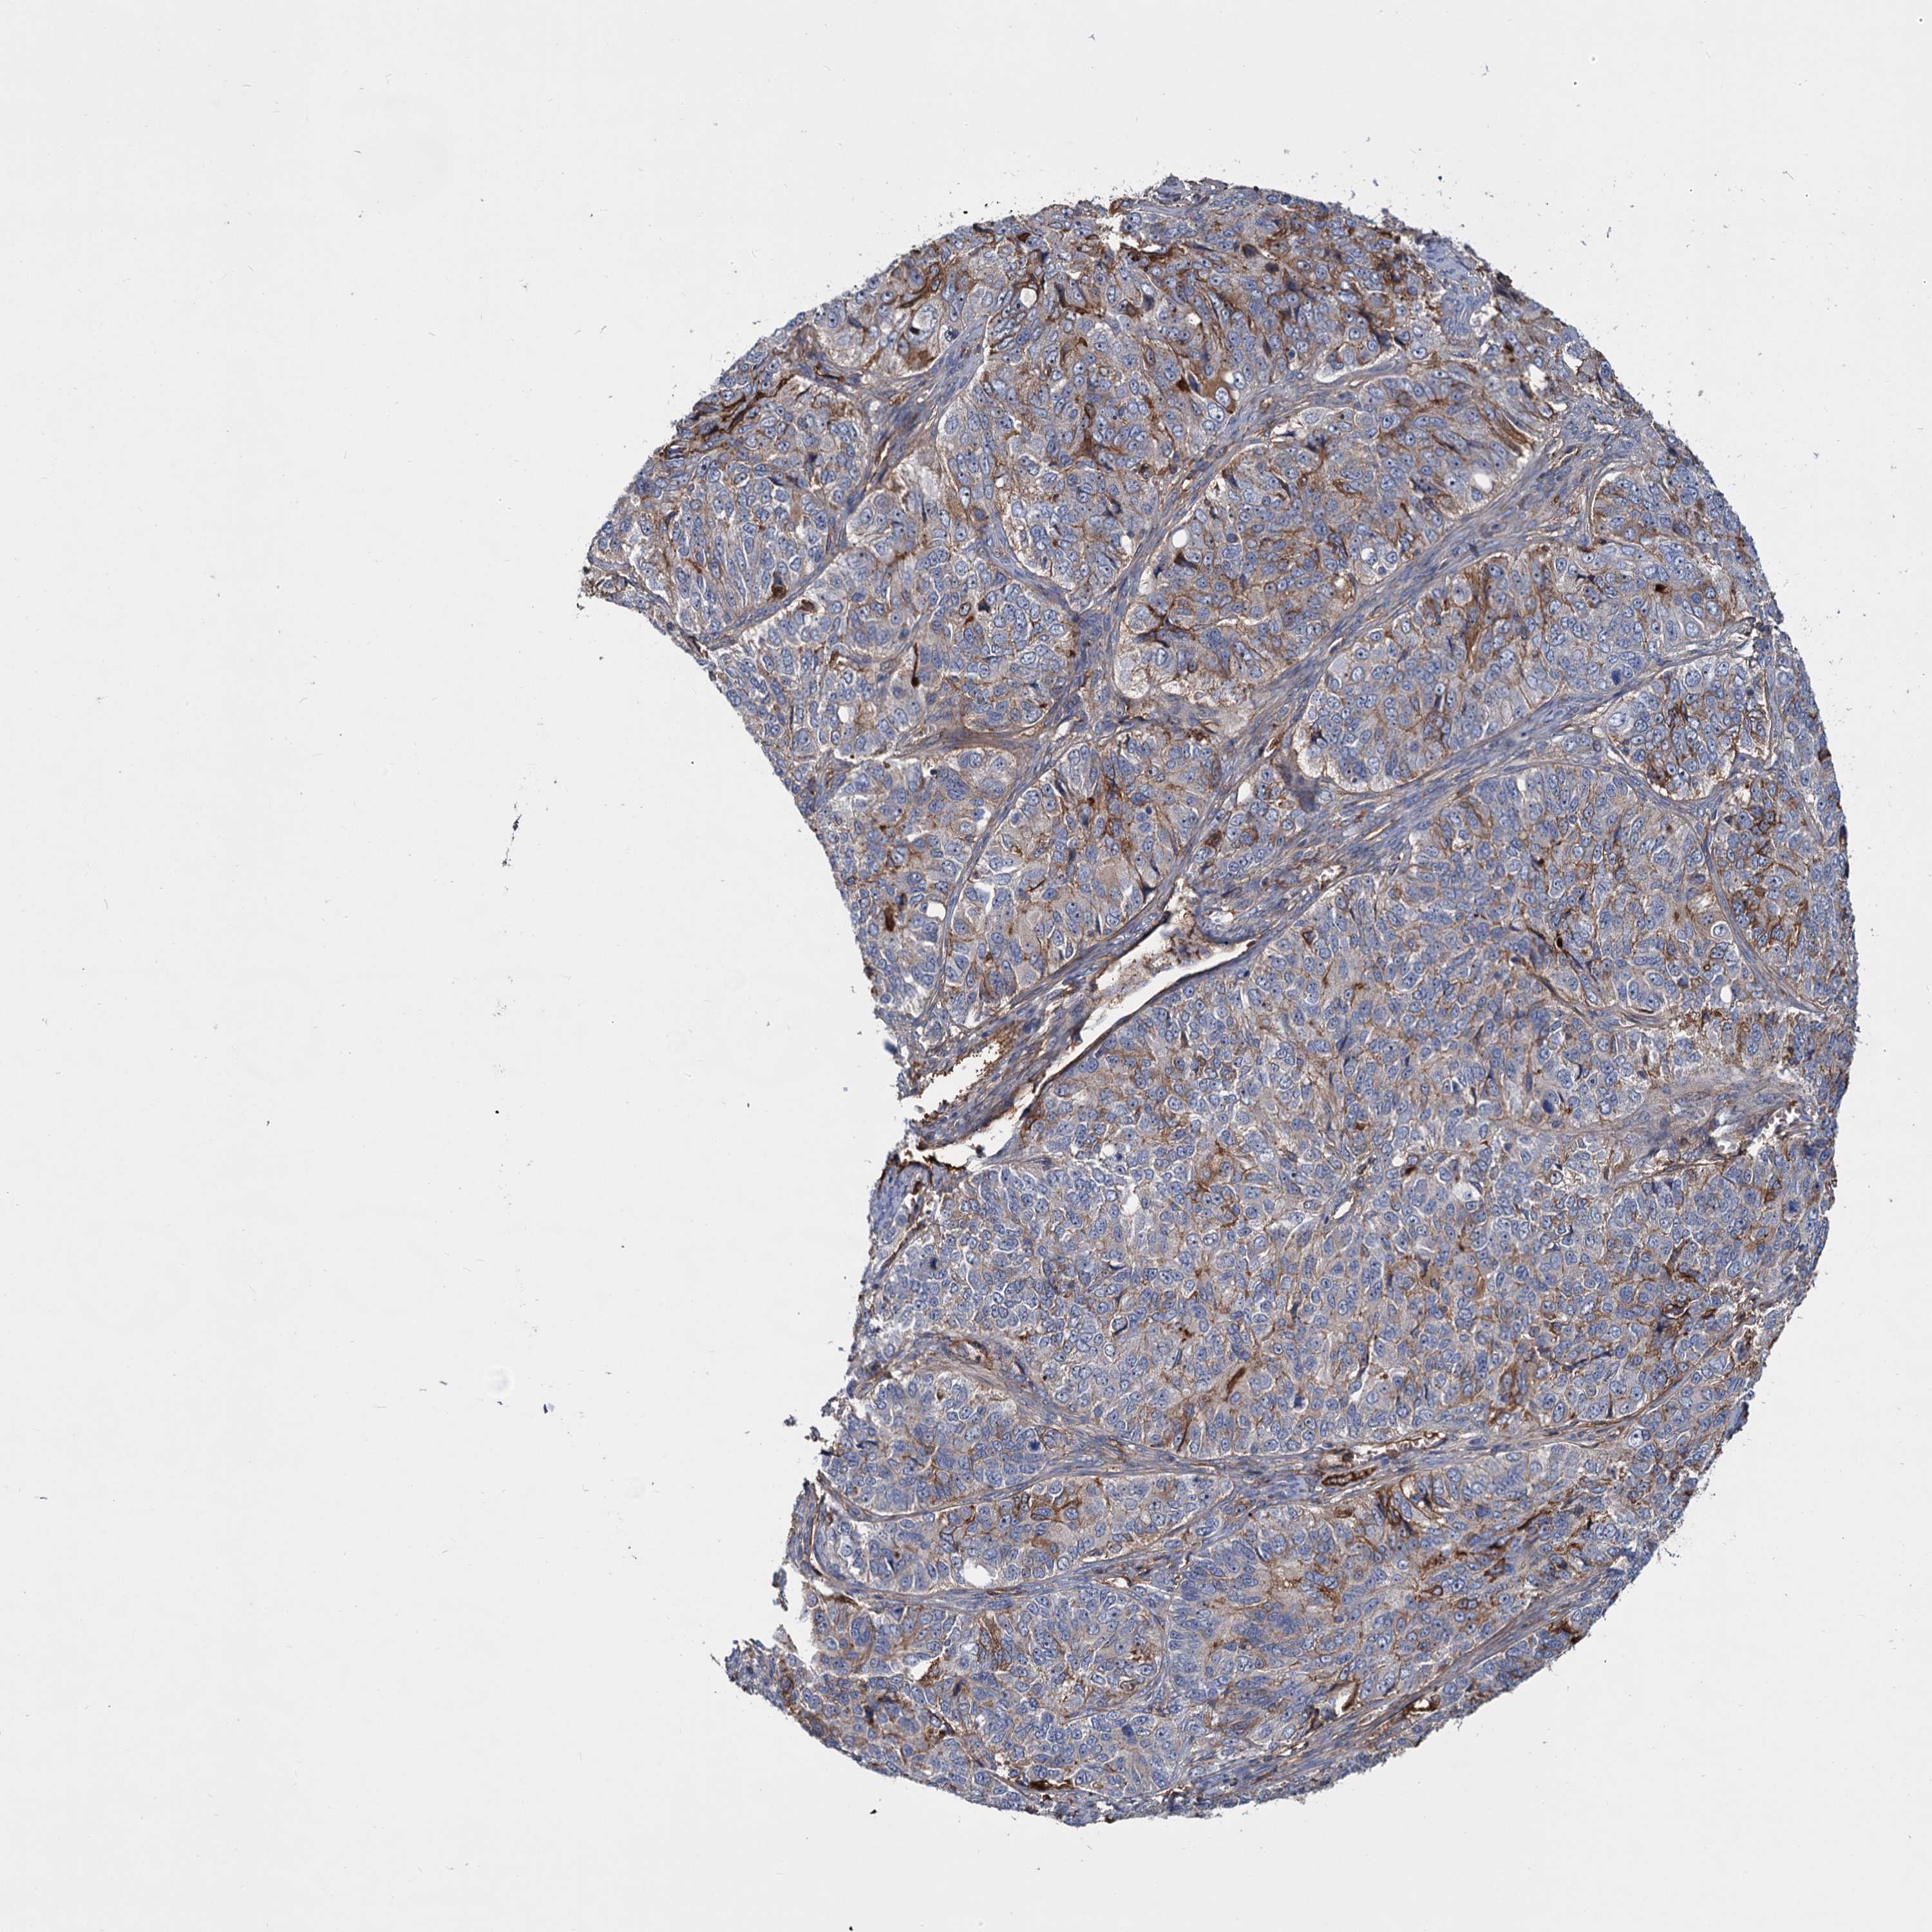

OVARIAN CANCER - Protein expressioni

A mouse-over function shows sample information and annotation data. Click on an image to view it in a full screen mode. Samples can be filtered based on level of antibody staining by selecting one or several of the following categories: high, medium, low and not detected. The assay and annotation is described here.

Note that samples used for immunohistochemistry by the Human Protein Atlas do not correspond to samples in the TCGA dataset.

Antibody stainingi

Antibody staining in the annotated cell types in the current human tissue is reported as not detected, low, medium, or high, based on conventional immunohistochemistry profiling in selected tissues. This score is based on the combination of the staining intensity and fraction of stained cells.

Each image is clickable and will lead to virtual microscopy that enables deeper exploration of all samples and also displays staining intensity scores, fraction scores and subcellular localization as well as patient and tissue information for each sample.

Antibody HPA035827

Staining

High

Medium

Low

Not detected

Intensity

Strong

Moderate

Weak

Negative

Quantity

>75%

75%-25%

<25%

None

Location

Nuclear

Cytoplasmic/membranous

Cytoplasmic/membranous,nuclear

Cystadenocarcinoma, serous, NOS

Carcinoma, endometroid

Cystadenocarcinoma, mucinous, NOS

Carcinoma, NOS